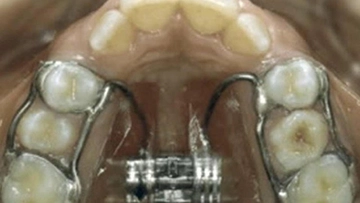

Çeneyi Nasıl İleri Alabilirim?Çene yapısı, yüz estetiği ve fonksiyonu açısından önemli bir rol oynamaktadır. Çenenin ileri ya da geri pozisyonu, yüz simetrisi, diş sağlığı ve genel estetik algı üzerinde belirleyici etkilere sahiptir. Bu makalede, çenenin nasıl ileri alınabileceği üzerine çeşitli yöntemler ve teknikler ele alınacaktır. 1. Ortodontik Tedavi YöntemleriOrtodontik tedavi, dişlerin ve çenenin düzgün bir şekilde hizalanmasını sağlamak amacıyla kullanılan bir yöntemdir. Çenenin ileri alınmasında aşağıdaki ortodontik yaklaşımlar etkili olabilir: